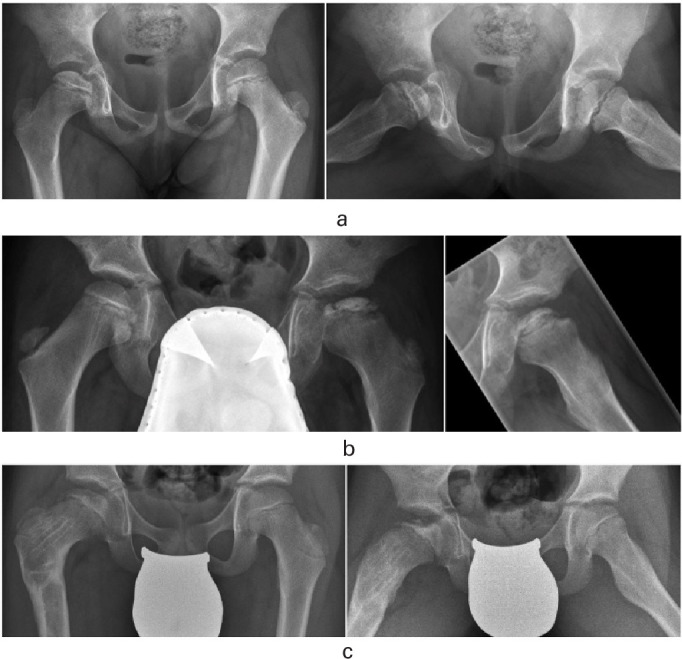

Abstract Image